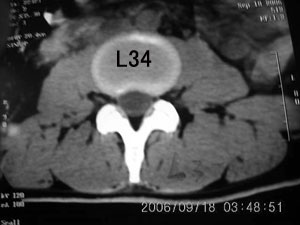

以下是引用守望可可西里在2006-9-18 21:29:00的发言:[br][br] 马尾肿瘤,密度较低,大部分似乎呈囊性变(看着很费眼),考虑室管膜瘤,建议mri。

以下是引用dyg在2006-9-18 22:27:00的发言:[br]正常脊髓.[br]分析:人的脊髓从枕大孔开始至腰1.2椎体为止,有2个生理膨大,分为颈膨大和腰膨大;该病人脊髓须然从腰段开始直至马尾似乎膨大,胆是与上段脊髓密度没有多大变化,所以我认为是正常膨大之延续;当然最好做ct增强或mri检查,排除肿瘤.

以下是引用飞虎在2006-9-18 20:18:00的发言:[br]部分椎管内密度不均且无ct值 故mri检查